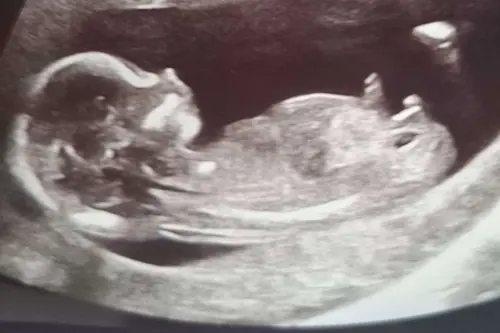

Jongen zeker

Jongetje!

Dit is een jongen

Jij hebt een mooie jongentje馃挋 Wat een mooie echo 馃槏 Door jou kan ik nu niet wachten tot ik mijn tweeling zo groot zie ik zie niks meer dan garnaal zo iets 馃槶 Zo leuk 馃樆 Gefeliciteerd met jongen 鉂わ笍鉂わ笍鉂わ笍鉂わ笍鉂わ笍鉂わ笍鉂わ笍鉂わ笍鉂わ笍鉂わ笍 Wat wilde jij eigenlijk 馃槏馃グ Of wat hoopte jij